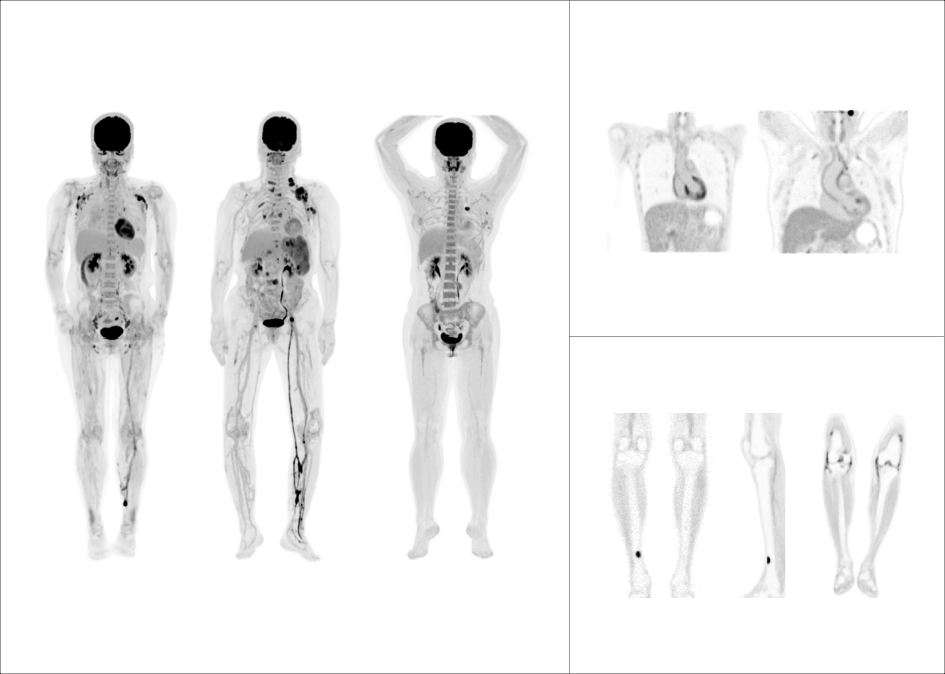

由精细向精准

全面刷新PET影像感官

由临床向科研探索

解锁更多应用新场景

支持68Ga、 90Y、18F、82Rb、15O等不同半衰期、不同核素药物高清显像